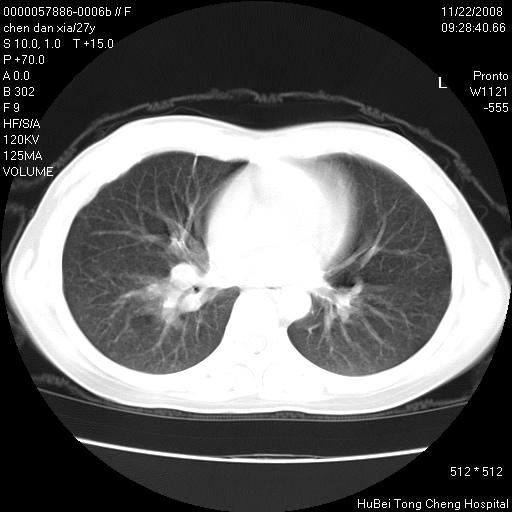

标题: CT16752:F,27Y。发热咳嗽20余天,伴盗汗。 [打印本页]

标题: CT16752:F,27Y。发热咳嗽20余天,伴盗汗。

考虑双肺粟粒性肺tb,右侧胸膜增厚.

右下肺见片絮状影,两肺野内分布不均的小结节影,结核并肺内播散可能性大,建议结合实验室检查 .

右下肺纹理模糊;纵隔可见肿大淋巴节;右心缘旁结节,边缘光滑,纵隔窗病变范围较肺窗明显小,首先考虑右下肺结核,不排外淋巴瘤

双肺纹影普多,部分呈网状,支炎或淋巴管炎?

纵隔内淋结肿

局部胸膜增厚

下肺结节,结节内钙化,肺门纵隔淋巴肿大 结核可能性大

似有粟米状结节。考虑粟粒型肺结核?

1)考虑两肺感染性病变。2)纵隔淋巴结肿大。